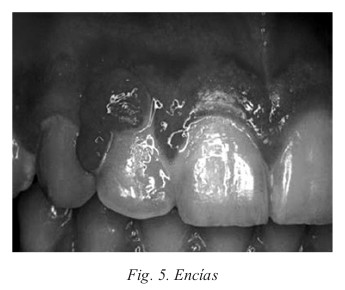

A. Boca

En las encías existe una hiperemia y edema que puede originar un sangrado con facilidad y puede producir gingivitis (inflamación de las encías). Es frecuente la gingivitis hipertrófica sangrante y dolorosa que se conoce con el nombre de épulis del embarazo. El épulis desaparece al finalizar la gestación pero en ocasiones suele necesitar extirpación quirúrgica. Estos cambios se deben a los niveles de estrógenos y hormona coriónica humana (HCG).